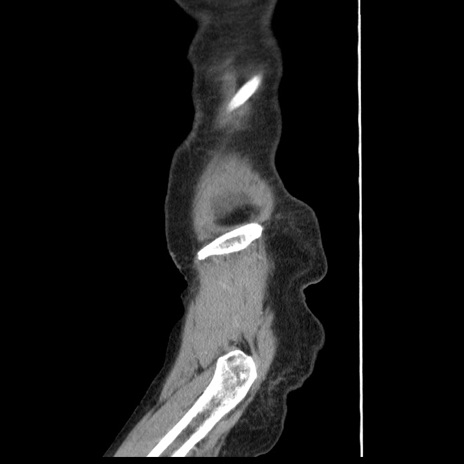

症例1(矢状断像)

【症例】80歳代女性

【主訴】腹痛

【現病歴】8時間前から腹痛あり来院。

【既往歴】糖尿病、脂質異常症、子宮体癌にて子宮全摘術

【身体所見】意識清明・会話良好だが腹痛で苦悶様、全腹部にわたって反跳痛と圧痛あり

【データ】WBC 13600、CRP 0.14、LDH 224、CK 90